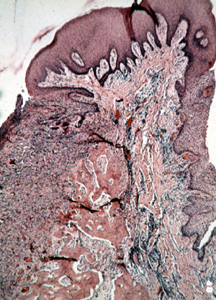

Esta

microfotografía de baja resolución muestravarios componentes del tejido. Hay áreas de tejido conjuntivo

celular y zonas de inflamación crónica. Además, usted puede ver las

numerosas trabéculas óseas que amenudo están presentes.

Ilustrado aquí

es el área central de tejido conjuntivo celular con el epitelio encima

y trabéculas de hueso al fondo. La presencia de hueso es común.

A menudo sepresentan cuerpos calcificados pequeños. (cementículos)

Casi

cualquier tipo de calcificación puede encontrarse en estas lesiones.